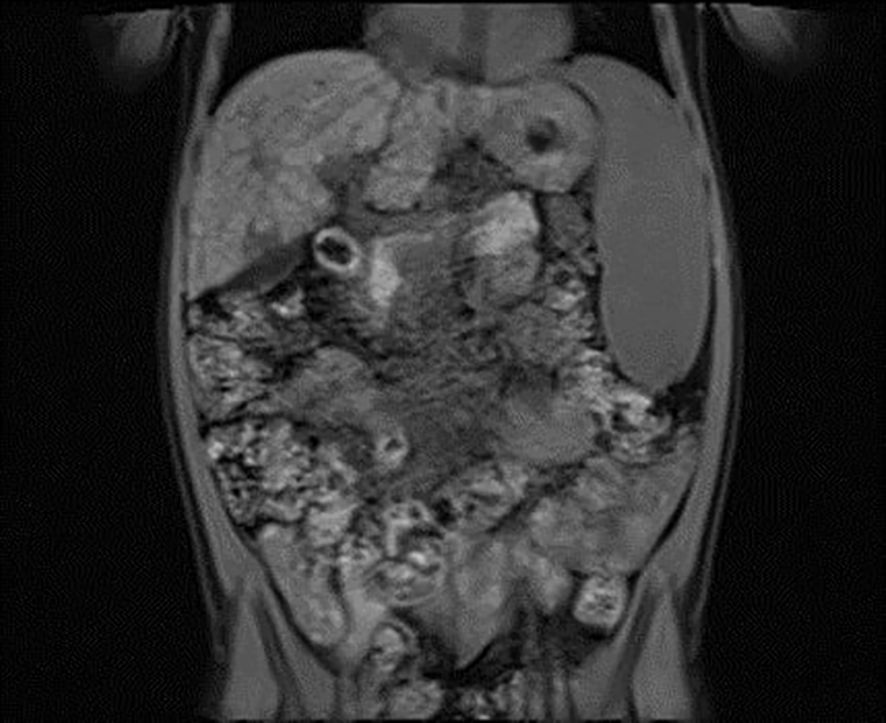

A 6-year-old girl was admitted to the Department of Pediatrics, Endocrinology, Diabetes with the Cardiology Division due to suspected diabetes mellitus. The parents reported a 4-day history of polyuria and polydipsia, along with a persistent acetone-like breath odor lasting two weeks after a respiratory infection. They did not observe any other concerning symptoms. According to the parents, the patient had no significant prior health issues, was not on any chronic medications, and had no known allergies. The family history was negative for diabetes mellitus. On admission to the Department, the general condition was good, with stable circulatory and respiratory function, logical contact, blood pressure of 91/48 mmHg, and a heart rate of 120 beats per minute (bpm). Physical examination revealed dry oral mucous membranes, a tongue coated with a white film, petechiae on the upper limbs, a distended abdomen, arched above the chest level, and increased bowel sounds. Laboratory findings showed significant abnormalities, including hyperglycemia (578 mg/dL), hyponatremia (128 mmol/L), hypochloremia (93 mmol/L), increased glycated hemoglobin fraction A1c (HbA1c; 9,29%), elevated liver enzyme levels, in gasometry features of compensated metabolic acidosis (pH = 7.38, HCO3 = 14.3 mmol/L, base excess [BE] = −9.8). Urinalysis revealed ketonuria (+++) and glucosuria (+++). Peripheral blood counts demonstrated pancytopenia confirmed on two occasions, with white blood cell counts dropping from 3.78 to 1.9 ×109/L, hemoglobin levels from 7.2 to 4 g/dL, and platelet counts from 35,000 to 22,000/μL. Laboratory findings showed coagulation abnormalities, including extended prothrombin time (PT) and activated partial thromboplastin time (APTT), reduced fibrinogen levels, and increased D-dimer concentrations. Diabetes mellitus and diabetic ketoacidosis were diagnosed. The performed additional laboratory tests revealed autoimmune markers for diabetes mellitus type 1, including anti-islet cell antibodies (ICA) at 160 Juvenile Diabetes Foundation (JDF) units and anti-glutamic acid decarboxylase autoantibodies (GADA) at 1779.41 U/mL. Hence, diabetes mellitus type 1 was diagnosed. The treatment included insulin therapy and intravenous electrolyte supplementation, achieving normalization of glycemia and improvement of gasometric values. Subcutaneous insulin therapy and a diabetic diet were initiated on the second day of hospitalization. Abdominal ultrasound revealed mild hepatomegaly and splenomegaly measuring 116 mm. Chest X-ray showed no significant abnormalities. Because of persistent pancytopenia, an oncohematology consultation was conducted. The patient received transfusions of irradiated leukocyte-depleted platelet concentrate and irradiated leukocyte-depleted red blood cell concentrate. Bone marrow biopsy did not indicate a proliferative process but indicated reactive changes. Testing for parvovirus B19 DNA in the bone marrow was negative. Celiac disease was confirmed by highly elevated titers of anti-tissue transglutaminase (tTG) antibodies, anti-deamidated gliadin peptide (DGP) antibodies, and anti-endomysial antibodies (EMA), results exceeded the upper limit of normal by 10-fold. A gluten-free diet was initiated. Microbiological diagnostics, including molecular testing, showed no evidence of active infection. Serological studies demonstrated slightly elevated anti-Epstein-Barr virus (EBV) antibodies in the immunoglobulin (Ig) M (IgM) class and significantly elevated IgG antibodies, along with low anti-severe acute respiratory syndrome coronavirus 2 (SARS-CoV-2) antibody levels. Respiratory antigen testing detected the presence of Haemophilus influenzae. The levels of lactate dehydrogenase (LDH) and uric acid were within normal limits. Echocardiography of the heart and thyroid ultrasound showed no abnormalities. Follow-up biochemical tests revealed elevated aminotransferase activity, increased bilirubin levels, decreased albumin levels with normal total protein levels, and slightly elevated ammonia levels. Coagulation assessment showed persistent hypofibrinogenemia, elevated D-dimer levels, and prolonged PT and APTT. Reduced activity of clotting factors VII, IX, XI, XII, and protein C was observed. Following gastroenterological, hematological, and immunological consultations, diagnostics were expanded to include an antinuclear antibody (ANA) panel, which yielded negative results. A significant decrease in complement components 3 (C3) and 4 (C4), elevated levels of IgG (32 g/L) and IgA, normal IgM levels, and normal IgG4 subclass levels were observed, along with lymphopenia in flow cytometry. Subpopulation analysis revealed decreased T lymphocyte counts, including cytotoxic T cells and NK cells, and a reduced percentage of memory T cells. Evaluation of T-cell maturation showed normal percentages of recent thymic emigrants (RTE) and regulatory T cells. B-cell maturation assessment revealed a slightly reduced percentage of switched memory B cells and an increased percentage of IgM-only memory B cells. The percentage of double-negative T cells (DNTC) was slightly elevated. Based on these results, intracellular perforin expression disorders and common humoral and cellular immune deficiencies, as well as complement component deficiencies, were excluded. A panel-based genetic study was ordered to investigate genes whose defects lead to primary immunodeficiency disorders (Additional file 3). Next-generation sequencing (NGS) was performed using the custom-designed SureSelect XT2 Panel (Agilent Technologies, Santa Clara, CA, USA), in a range of genes related to inborn errors of immunity. Sequencing libraries were prepared according to the manufacturer’s protocol and set on the NextSeq 550 platform in the process of a 300-base-pairs (bp) paired-end run (Illumina, San Diego, CA, USA). The data analyses of the target regions were performed using Burrows-Wheeler Aligner Genome Alignment Software and the GATK Variant Caller algorithms and mapped to the human genome reference sequence GRCh37/hg19. The results were next analyzed using Variant Studio v.3.0 (Illumina), SureCall v.4.1 (Agilent Technologies), and Integrative Genomics Viewer v.2.3. The filtering criteria included coverage with at least 20 reads and a minor allele frequency (MAF) below 0.01 in the GnomAD database. Bioinformatic predictions were conducted using the Mutation Taster, SIFT, and PolyPhen platforms. The pathogenicity was determined according to the American College of Medical Genetics (ACMG) classification rules. The analysis did not identify any pathogenic or potentially pathogenic variants. In the anti-tissue antibody panel, positive anti-smooth muscle antibodies (ASMA) and a strongly positive result for anti-liver cytosol antigen type 1 (LC1) antibodies were detected. Differential diagnosis excluded hepatitis A, hepatitis B, hepatitis C, alpha-1 antitrypsin deficiency, and Wilson’s disease, with serum ceruloplasmin levels and urinary copper excretion within normal ranges. IgG4 levels were within normal limits. Urinary bile acid analysis via gas chromatography-mass spectrometry (GC-MS) ruled out inherited metabolic defects. Abdominal Doppler ultrasound excluded portal system thrombosis and revealed a nodular liver with increased stiffness and signs of portal hypertension. Elastography using the S-Shearwave method yielded a METAVIR fibrosis stage F4 – 54.2 kPa, with an interquartile range (IQR) of 18.7%. Gastroscopy excluded esophageal varices and revealed macroscopic changes typical of celiac disease. Magnetic resonance cholangiopancreatography (MRCP) confirmed micronodular cirrhosis with moderate biliary changes (Figures 1, 2). Based on the overall clinical picture and additional test results – significantly elevated alanine transaminase (ALT), hypergammaglobulinemia, high IgG levels, presence of autoantibodies, and exclusion of other causes of chronic liver pathology – autoimmune hepatitis was diagnosed. In the following year, the diagnosis was confirmed by a core needle liver biopsy performed at the Children’s Memorial Health Institute (CMHI). Platelet-bound IgG and IgM on platelets were detected using the direct immunofluorescence (DIF) test. This test, combined with the earlier exclusion of other possible causes of low platelet count, led to the diagnosis of immune thrombocytopenia. Consequently, the patient was diagnosed with a multi-organ autoimmune disease (APS-4; diabetes mellitus type 1, celiac disease, immune thrombocytopenia, autoimmune hepatitis with cirrhosis; Table 1).

Figure 1

MRI scan showing a cross-sectional view of the abdomen, displaying organs and tissues. Multiple dark and light areas indicate varying densities, with detailed visualization of an internal mass and surrounding structures.

Figure 1. Vertical plane image from magnetic resonance cholangiopancreatography (MRCP) presenting micronodular cirrhosis with moderate biliary changes.